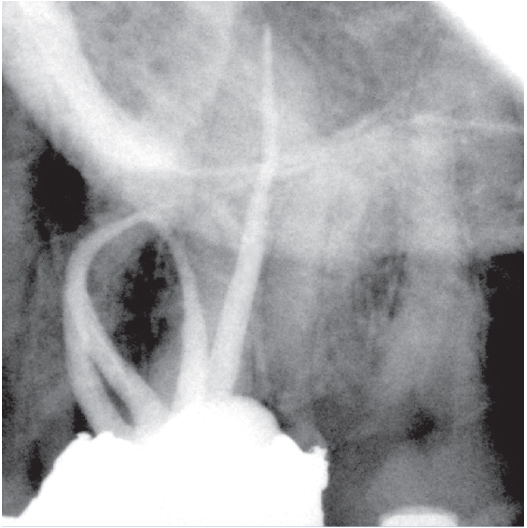

After

After Root Canal treatment